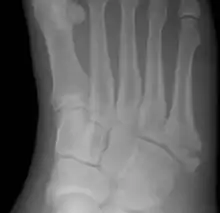

Jones fracture

A Jones fracture is a break between the base and middle part of the fifth metatarsal of the foot.[8] It results in pain near the midportion of the foot on the outside.[2] There may also be bruising and difficulty walking.[3] Onset is generally sudden.[4]

| Jones fracture as seen on Xray | |

The fracture typically occurs when the toes are pointed and the foot bends inwards.[6][2] This movement may occur when changing direction while the heel is off the ground such in dancing, tennis, or basketball.[9][10] Diagnosis is generally suspected based on symptoms and confirmed with X-rays.[3]